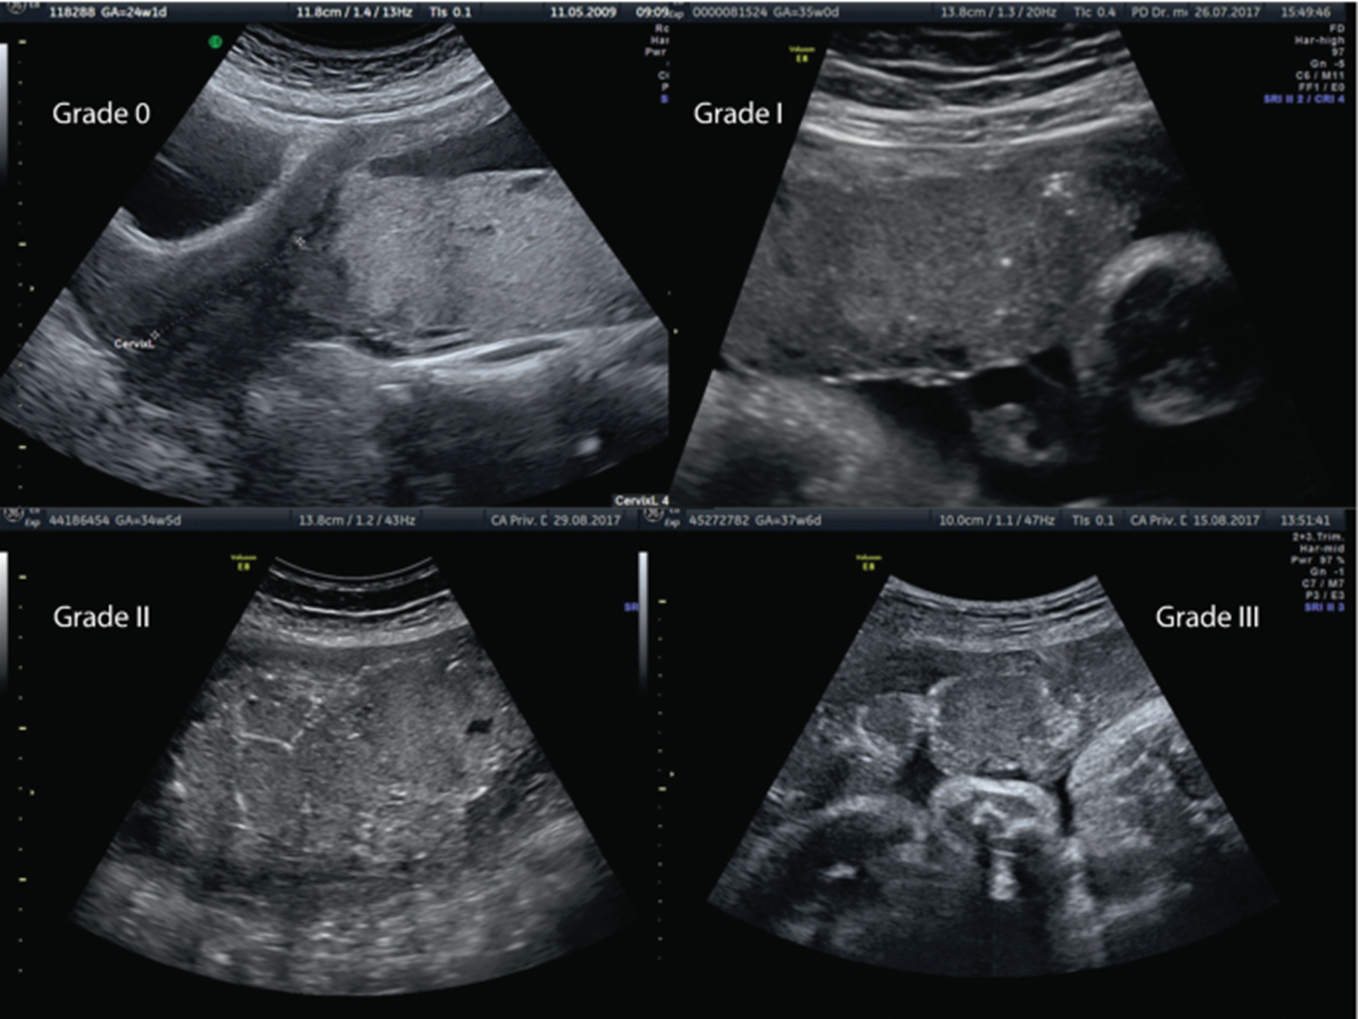

cisterna magna should be less than

1cm